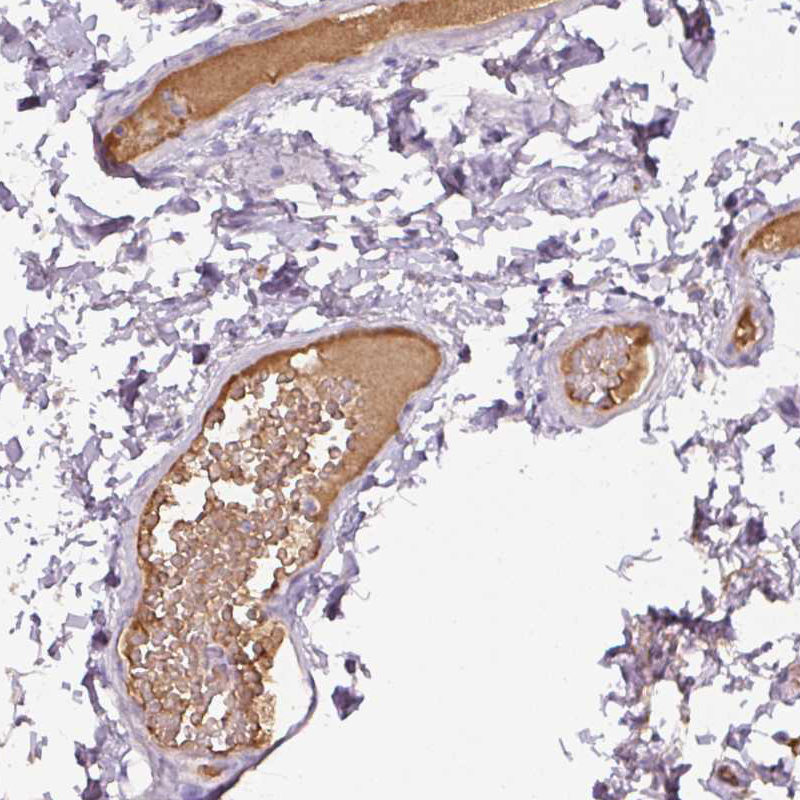

Immunohistochemical staining of human colon shows moderate positivity in plasma.